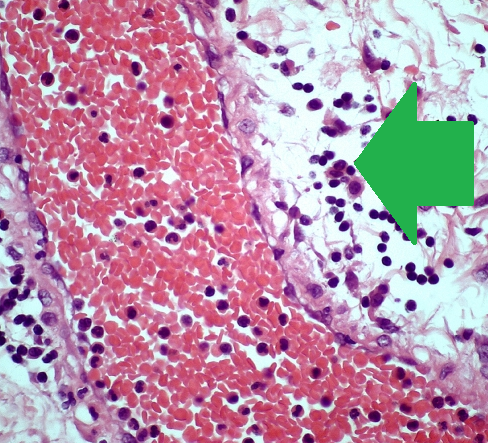

Φωτομικρογραφία ιστολογικής τομής χρωματισμένης με αιματοξυλίνη και ηωσίνη που αποκαλύπτει τα νευροενδοκρινικά κύτταρα του όγκου (Ευγενική παραχώρηση Dr. V. Penopoulos)